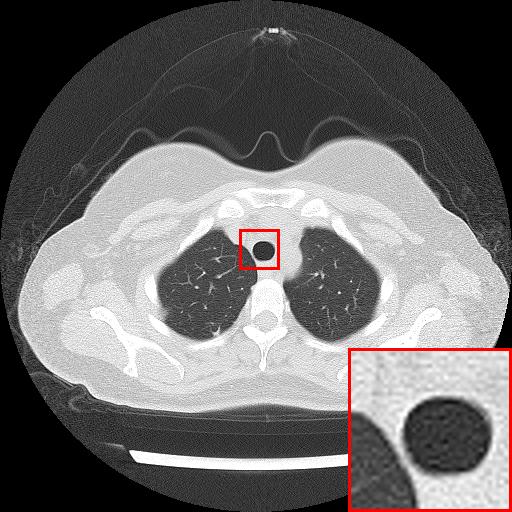

Figure 3: Reconstruction results of each algorithm for MRI images of the knee.

We likewise give the visualization comparison results for each comparison algorithm, as shown in Fig. 3 and Fig. 4. It can be seen that the reconstructed images based on bicubic interpolation and deep learning based EDSR and WDSR both show oversmoothing phenomenon and some loss of detail information of the images. In contrast, our T-GAN performs better for the reconstruction of detail information due to the texture Transformer structure.